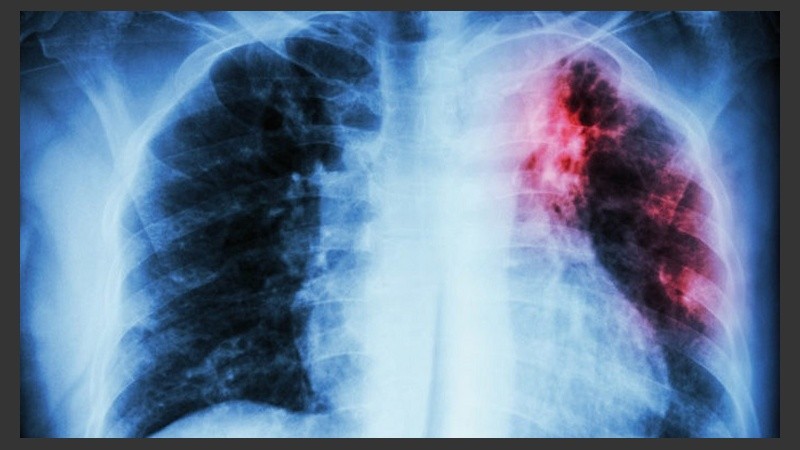

No obstante, esta enfermedad que afecta a los pulmones y se transmite por la expectoración de pequeñas partículas, sigue siendo una de las 10 primeras causas de muerte en el mundo, indicaron en el informe.